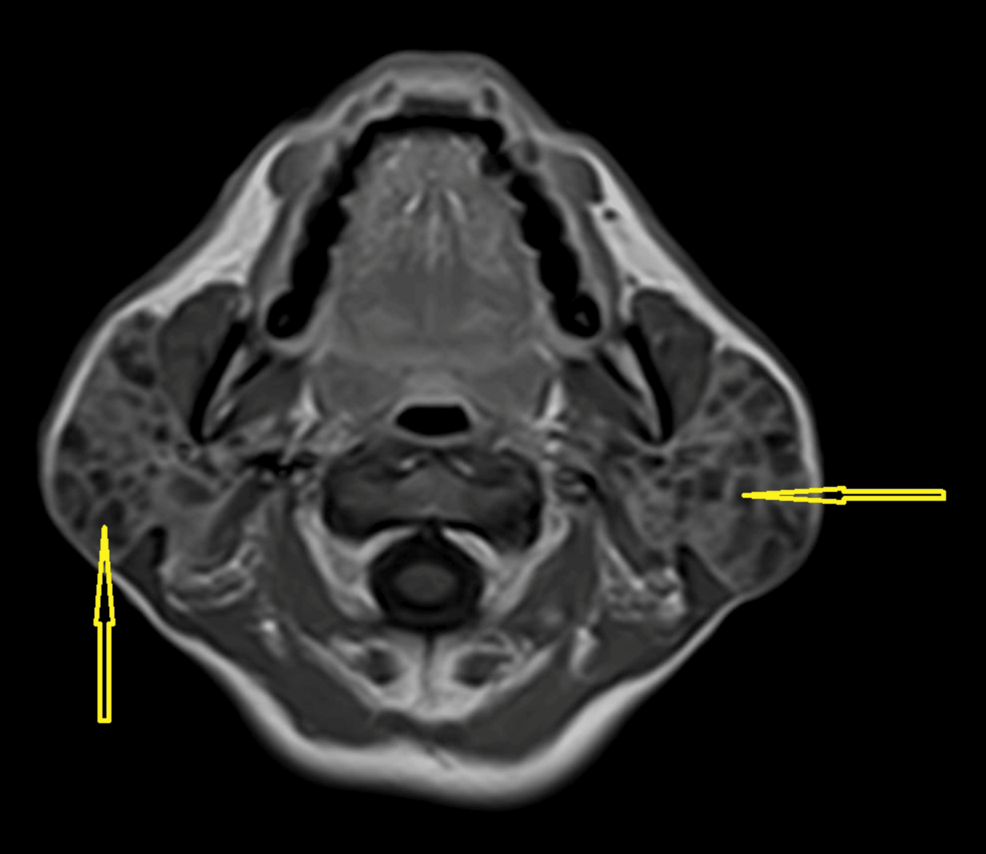

Polycystic Disease of Salivary Glands: Bilateral Parotid Enlargement